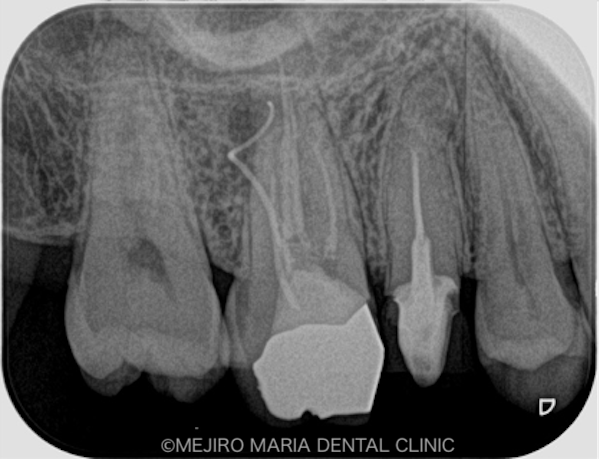

|治療詳細1.jpg)

右上6番の歯に確認できたフィステル(瘻孔)は、2回目の根管治療の際にはすでに消失していました。患者様のご希望により、すでに根管治療がされている手前側の歯(右上5番)も、根管治療をやり直すこととなりました。